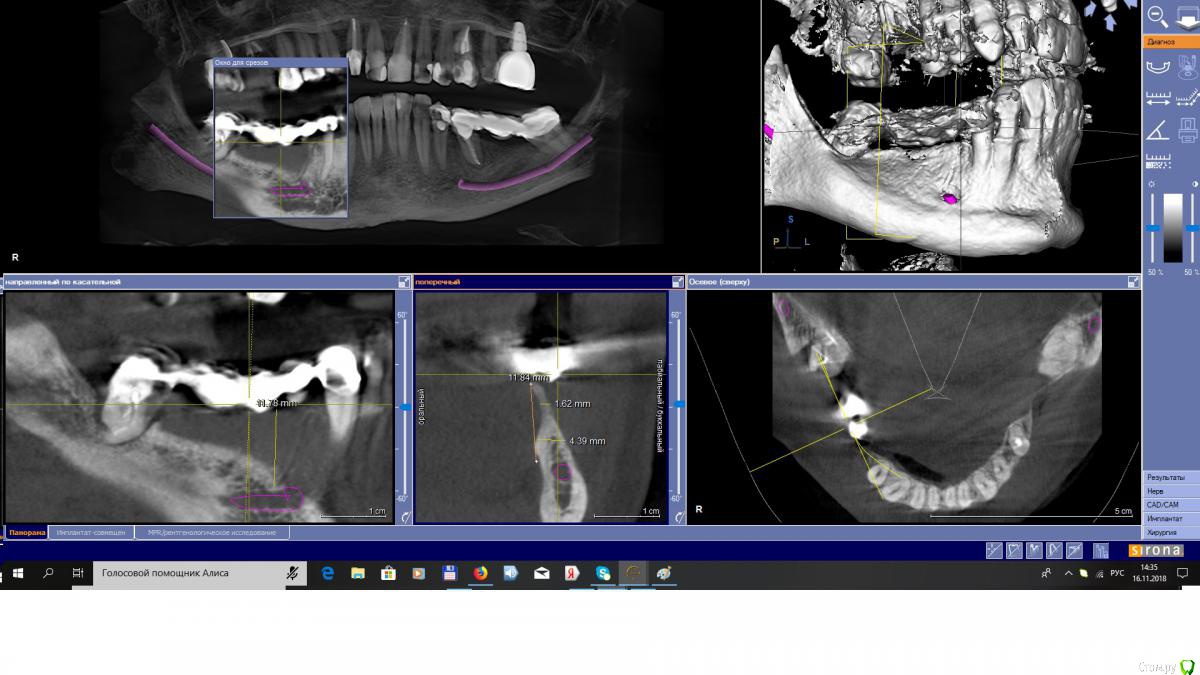

EEcho Опубликовано 16 ноября, 2018 Поделиться Опубликовано 16 ноября, 2018 Коллеги, добрый день!Ваши варианты при такой атрофии. Ссылка на комментарий

EEcho Опубликовано 22 ноября, 2018 Автор Поделиться Опубликовано 22 ноября, 2018 Это понятно, что можно любую методику кроме расщепления и моноблоков, но как в этом случае обойти ментальное отверстие с выходом сосудисто-нервного пучка почти вертикально? Резать мембрану обходя отверстие и бить кнопки вокруг, то есть сосиську по Урбану, с эволюшкой.? или делать каркас из мини пластин.? полужестким каркасом отверстие будет не обойти.( возможно графт будет через него высыпаться или врастет через него соединительная ткань)? Ссылка на комментарий

АнтонТЛТ Опубликовано 22 ноября, 2018 Поделиться Опубликовано 22 ноября, 2018 Если ментальное отверстие напрягает, нарастить до него и поставьте имплантат покороче 1 Ссылка на комментарий